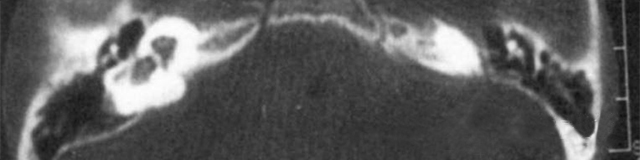

主要根據(jù)聽力學(xué)表現(xiàn)和影像學(xué)檢查。通過高分辨CT可看到耳蝸畸形。內(nèi)耳MRI顯示膜迷路內(nèi)水充盈,耳蝸扁平,耳蝸第二圈與頂圈間隔缺損,以及半規(guī)管、前庭的畸形。

先天性耳蝸畸形伴前庭和外半規(guī)管發(fā)育不良